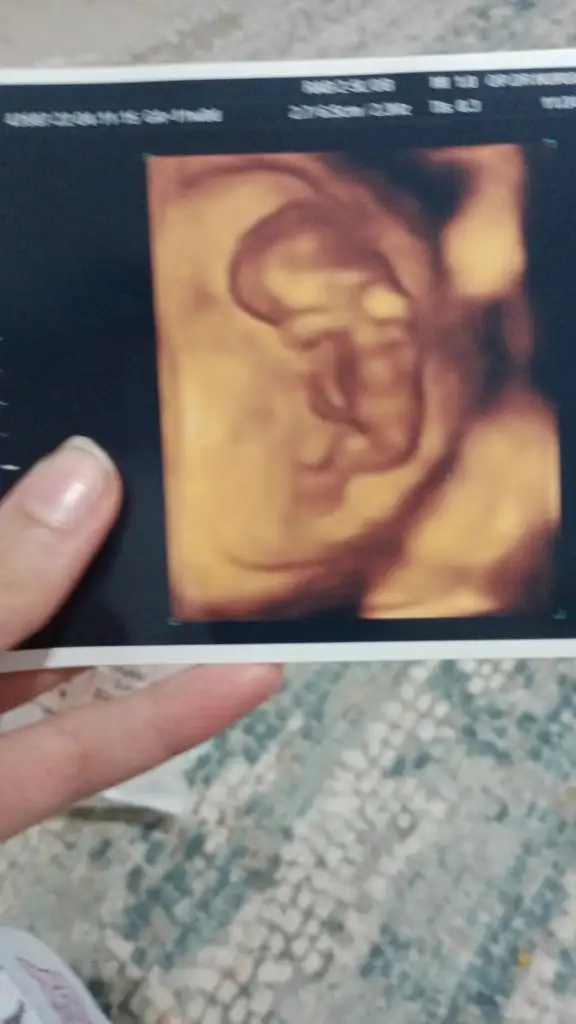

5 ve 14. haftaya kadar olan ultrason fotolarınızı paylaşın. Vajinadan mı yoksa karından mı çekildiğini ve kaç haftalık olduğunu da mutlaka belirtin.:anneadayı:

9+2 den selam sence ne olacak canım merak ettim 😌